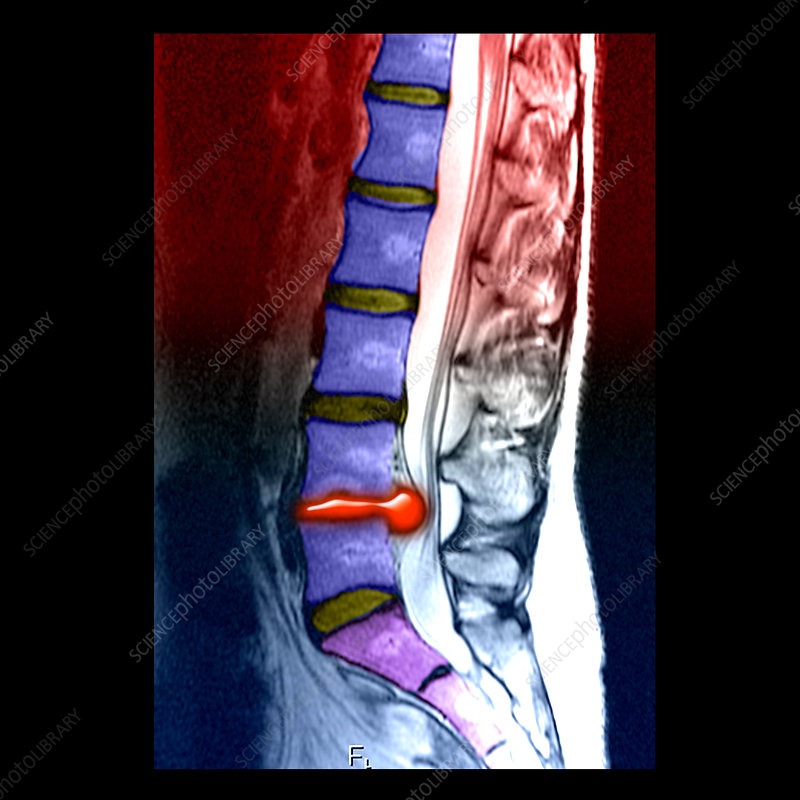

Chiropractic care has become an increasingly popular treatment option for individuals suffering from disc herniations. A herniated disc occurs when the soft inner portion of a spinal disc bulges out through a tear in the outer layer, often compressing nearby nerves and causing pain, numbness, or weakness. Chiropractors are trained to assess spinal misalignments and nerve interference, offering non-invasive solutions that can reduce discomfort and improve mobility. According to Harvard Health Publishing, chiropractic adjustments can relieve musculoskeletal pain, including that caused by herniated discs, by improving spinal alignment and reducing pressure on nerves ("Chiropractic Care for Pain Relief").

One common chiropractic technique used to treat disc herniations is spinal manipulation. This involves carefully controlled movements to restore normal motion to the spine and reduce nerve compression. For example, the Activator Method uses a small handheld device to deliver gentle, targeted impulses to the spine, which may be less likely to aggravate herniated disc symptoms compared to traditional manual adjustments ("Activator Method Chiropractic Technique"). Chiropractors may also employ flexion-distraction techniques, which use a specialized table to stretch and decompress the spine, allowing the herniated material to retract and relieve nerve pressure. These treatments are often considered safer and less invasive than surgical options.